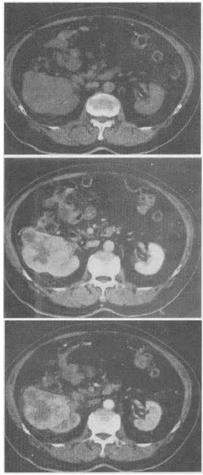

患者,男,51岁。右肾区不适4个月余,有镜下血尿。CT扫描结果见图。最有可能的诊断是()。

A、肾癌

B、肾盂癌

C、肾错构瘤

D、肾结核

E、肾腺瘤

A